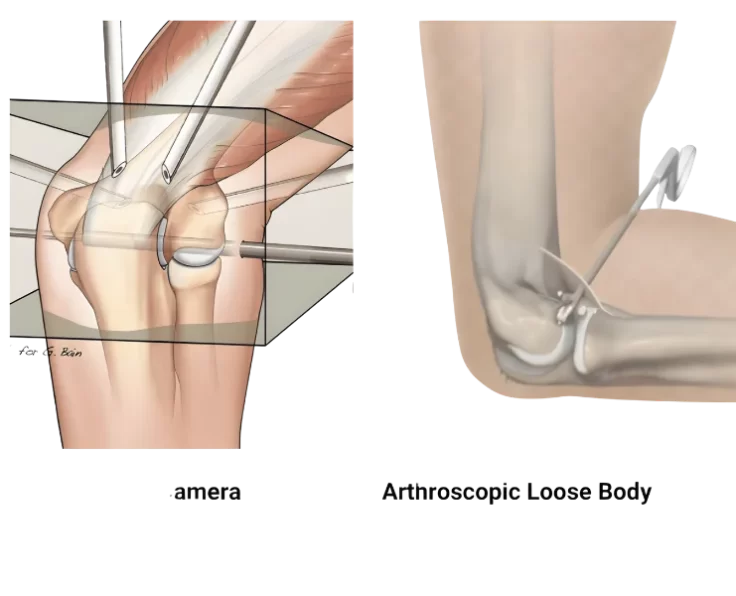

Elbow Arthroscopic Removal of Loose Bodies

Arthroscopic debridement of the elbow is a treatment procedure used to examine, diagnose, and correct abnormalities within the elbow joint.

Elbow Arthroscopic Debridement

Loss of motion in the elbow joint can be caused by a variety of factors, the most common of which is elbow trauma.

The operation is used to alleviate pain, eliminate locking, and increase elbow joint mobility. We do this operation as an arthroscopic procedure, despite the fact…

Elbow Arthroscopy OK Procedure

Elbow Arthroscopy

The term arthroscopy comes from Greek words that refer to the joint. In modern surgery, your surgeon uses a small camera and a video monitor…